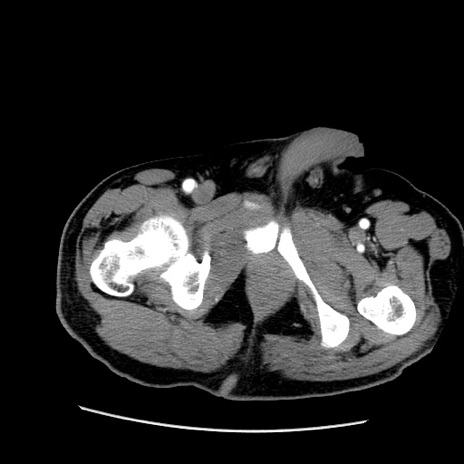

症例22(横断像)

【症例】50歳代男性

【主訴】腹痛

【現病歴】AVMからの被殻出血のため回復期リハ病棟入院中。 本日午後3時頃急に下腹部痛が出現した。

【既往歴】AVM、被殻出血、虫垂炎、高血圧

【身体所見】意識晴明、左半身不全麻痺、会話の理解は良好、36.5°C、腹部:膨隆、全体に板状硬、下腹部正中に圧痛点あり、反跳痛-、筋性防御不明、右下腹部にope scar

【データ】WBC 9400、CRP 0.06